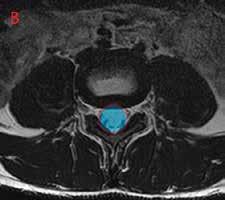

Tyypillinen paikka kulumaperäiselle siirtymälle on lannerangan toiseksi alin L4/5-väli, ja on ajateltu joidenkin paikallisten anatomiaan liittyvien tekijöiden voivan selittää siirtymän syntyä (kuva 1A). Tiedetään myös, että kulumaperäinen siirtymä on naisilla yleisempi kuin miehillä eli jokin sukupuoleen liittyvä selittävä tekijäkin on olemassa.

Kuva 1. Magneettikuvat lannerangasta seisovassa asennossa sivusuunnasta katsottuna. Kuvassa A näkyy L4-nikaman kulumaperäinen siirtymä eteenpäin (nuoli). Välilevy nikamasiirtymän kohdalla on madaltunut kulumamuutoksena. Kuvassa B näkyy rasitusmurtuman pohjalta syntynyt nikamasiirtymä L5-nikamassa (nuoli). Myös tässä siirtymävälin välilevy on madaltunut kuluman seurauksena.

Kulumaperäisessä siirtymässä koko nikama siirtyy eteenpäin, jolloin nikaman takakaaret herkästi ahtauttavat selkäydinkanavaa (kuva 2). Siirtymä on useimmiten kooltaan pieni, mutta pienikin muutos voi aiheuttaa selkäydinkanavan ahtautumista ja siitä syntyviä alaraajoihin säteileviä ahtaumaoireita, kuten kipua, katkokävelyä, tunnon ja lihasvoiman heikentymistä. Kooltaan suurempia siirtymiä tavataan harvemmin. Niihin liittyy usein paitsi ahtaumaoireita, myös selän epätukevuusoireita, kuten säväyttelevää puukoniskumaista selkäkipua.

Kuva 2. Magneettikuvat poikkileikkeinä selällään makaavasta henkilöstä. Selkäydinkanavan pinta-ala on merkitty kuviin läpikuultavalla varjostuksella punaisen ääriviivan sisällä. Kuvassa A nähdään voimakasasteinen selkäydinkanavan ahtaus L4/5-välissä. Kyse on samasta henkilöstä kuin kuvassa 1A. Kuvassa B näkyy nuoren henkilön normaalilaajuinen selkäydinkanava L4/5-välissä.